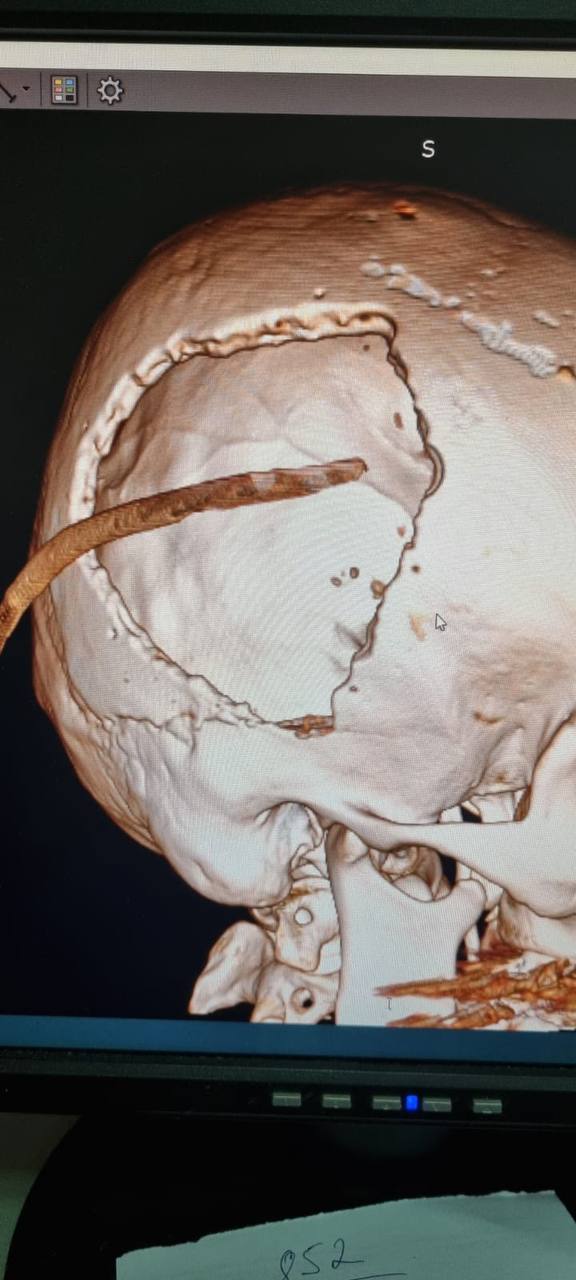

В больнице выяснилось: у пациента перелом черепа и массивная эпидуральная гематома (около 70 мл крови), сдавливающая мозг и вызвавшая отек и смещение его структур. Это крайне опасное состояние: такие гематомы встречаются реже чем у 2% всех черепно-мозговых травм, поэтому каждая минута промедления может стоить жизни. После операции ессентучанин оставался в глубокой коме и не было никаких гарантий, что он выживет. Но на десятый день мужчина все-таки пришел в сознание и даже начал дышать сам. Сегодня он чувствует себя отлично и уже готовится к выписке после второй операции.